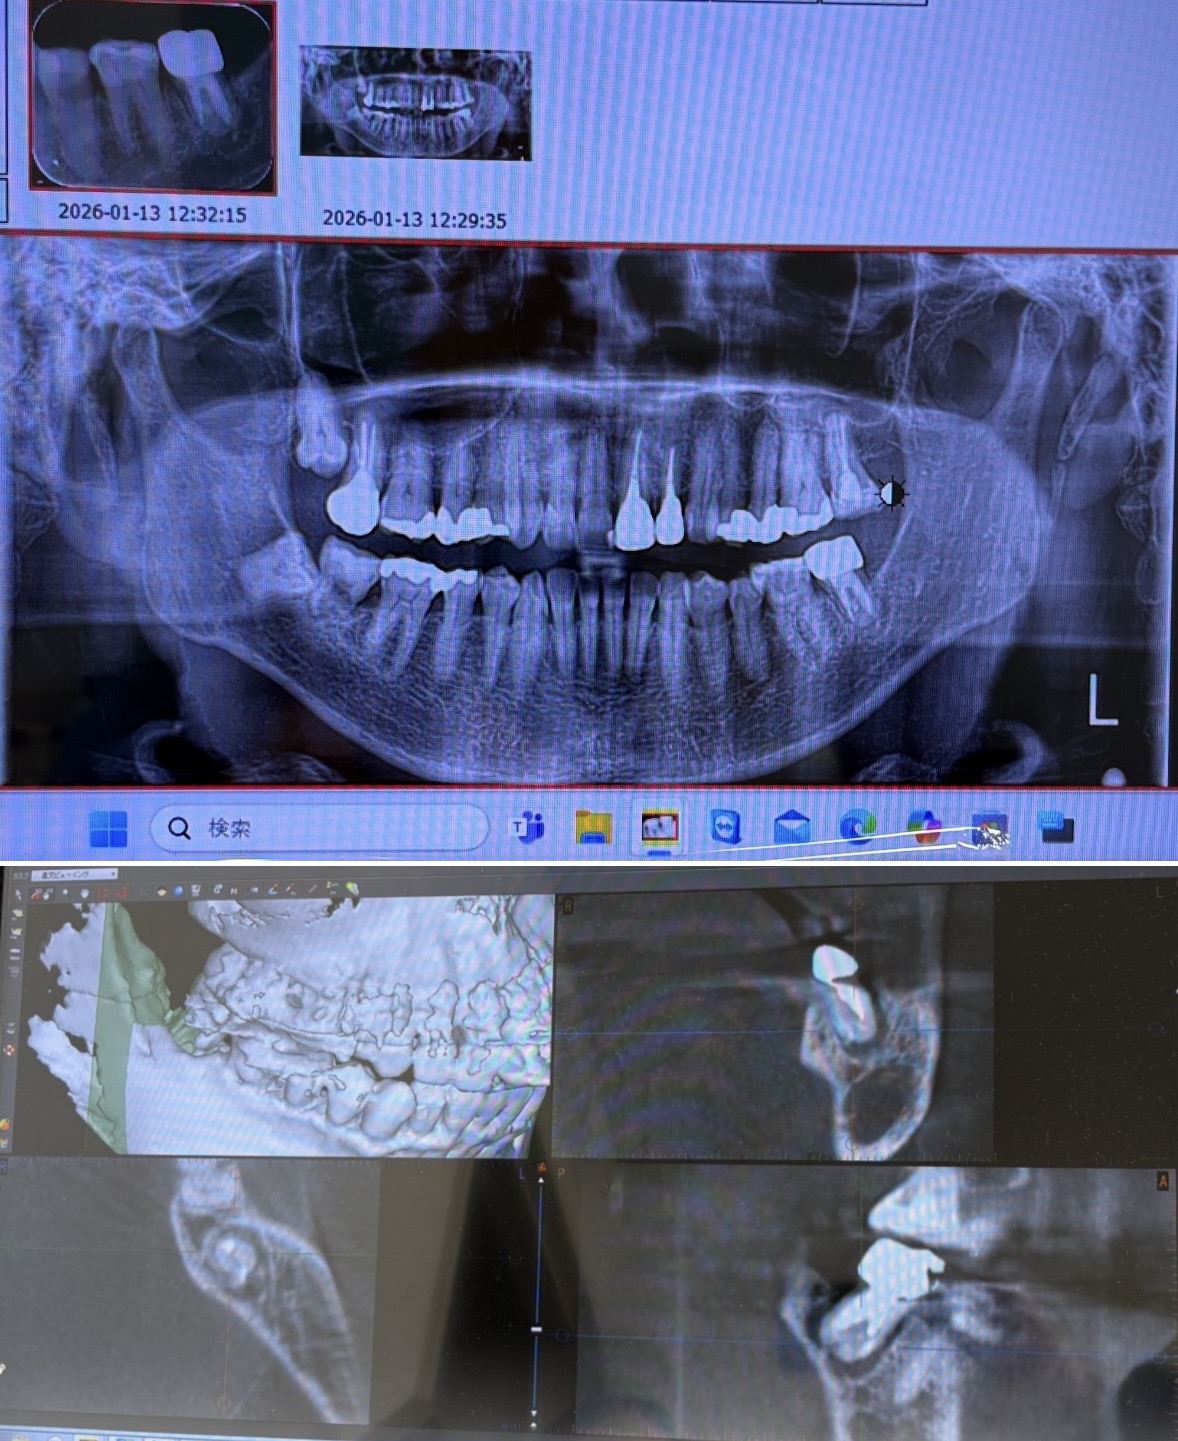

1月13日、CT持ってる歯科医院行き撮影 。

CTで歯の根の周りが袋状になっていて、骨が吸収されているとCT持ってる歯科医院では言われましたが、膿が溜まっていると画像でわかると思うのですが、違う見解はあるのでしょうか?

画像のアップはしようとしても最初の投稿しかできないようなので、こちらに投稿させていただきました

画像1